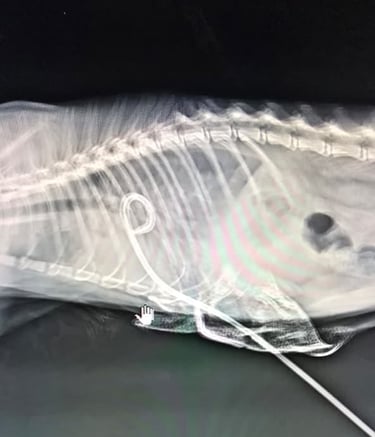

Investigations, including X-ray and ultrasound, revealed a severe pyothorax — a collection of pus and fluid in the chest cavity. Despite repeated aspirations of over 250ml each time, the fluid continued to accumulate, indicating the need for a more advanced intervention.

Our veterinary team employed a pig-tail catheter in the pleural cavity for continuous drainage under sedation and anesthesia. This approach allowed controlled and gentle removal of the infection, helping Mango breathe comfortably and recover steadily.